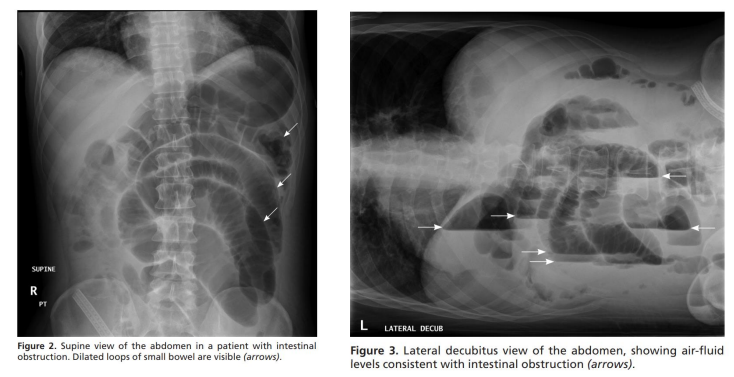

2.3. Chẩn đoán bằng X quang bụng (ASP)

- Bộ ba trong tắc ruột muộn:- Nhiều mức nước-hơi,

- Giãn các quai ruột non, và

- Không có khí trong đại tràng

- Độ nhạy và đặc hiệu thấp (độ nhạy 70%)

- Liềm hơi dưới hoành → biến chứng thủng

- Nhược điểm:- Không phát hiện ra các dấu hiệu sớm của viêm phúc mạc hoặc thắt nghẹt ruột;

- Không phân biệt được các nguyên nhân tắc